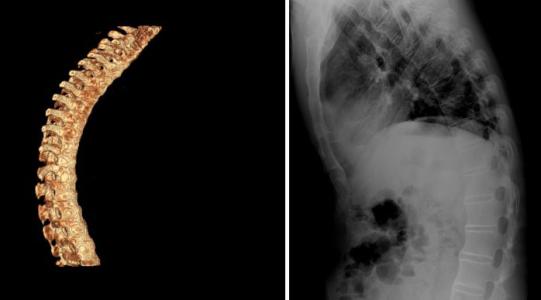

怎样预防强直性脊柱炎的危害?需做好以下三点

说起强直性脊柱炎,很多朋友都只知道这是一种骨科疾病,会导 ...

成都强直性脊柱炎医生,你了解强直性脊柱炎的具体预防环节吗

在强直性脊柱炎疾病发生之前,为了避免不必要的伤害,我们一定要 ...